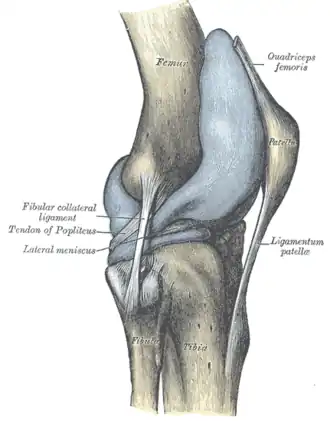

Extracapsular

The patellar ligament connects the patella to the tuberosity of the tibia. It is also occasionally called the patellar tendon because there is no definite separation between the quadriceps tendon (which surrounds the patella) and the area connecting the patella to the tibia.[23] This very strong ligament helps give the patella its mechanical leverage[24] and also functions as a cap for the condyles of the femur. Laterally and medially to the patellar ligament, the lateral and medial retinacula connect fibers from the vasti lateralis and medialis muscles to the tibia. Some fibers from the iliotibial tract radiate into the lateral retinaculum and the medial retinaculum receives some transverse fibers arising on the medial femoral epicondyle.[10]: 206

The medial collateral ligament (MCL a.k.a. "tibial") stretches from the medial epicondyle of the femur to the medial tibial condyle. It is composed of three groups of fibers, one stretching between the two bones, and two fused with the medial meniscus. The MCL is partly covered by the pes anserinus and the tendon of the semimembranosus passes under it.[10]: 206 It protects the medial side of the knee from being bent open by a stress applied to the lateral side of the knee (a valgus force).[10]: 206

The lateral collateral ligament (LCL a.k.a. "fibular") stretches from the lateral epicondyle of the femur to the head of fibula. It is separate from both the joint capsule and the lateral meniscus.[10]: 206 It protects the lateral side from an inside bending force (a varus force). The anterolateral ligament (ALL) is situated in front of the LCL.

Lastly, there are two ligaments on the dorsal side of the knee. The oblique popliteal ligament is a radiation of the tendon of the semimembranosus on the medial side, from where it is direct laterally and proximally. The arcuate popliteal ligament originates on the apex of the head of the fibula to stretch proximally, crosses the tendon of the popliteus muscle, and passes into the capsule.[10]: 206

Illustrations

Left knee-joint from behind, showing interior ligaments. -

Capsule of right knee-joint (distended). Lateral aspect. -